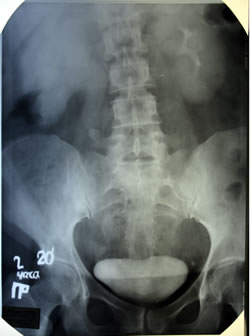

ОБЗОРНАЯ

И ЭКСКРЕТОРНАЯ УРОГРАФИЯ: |

|